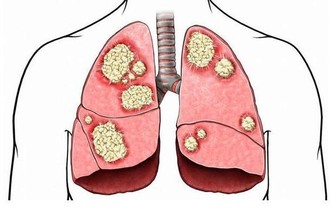

患者拿著報告單,難以置信,他劇烈地搖著腦袋,他的妻子一直用手摀住嘴巴哭個不停,她同樣不敢相信這一切都是真的,35歲,上有老下有小,正處於事業的穩定期,但是誰又會相信,本該是一個男人風華正茂的時候,小楊,卻被宣布患上了胰腺癌,而且是晚期,癌細胞已經轉移到肝臟和腹膜,並引起了腹腔積液!

醫學上,胰腺癌是一種惡性程度很高,診斷和治療都很困難的消化道惡性腫瘤,約90%為起源於腺管上皮的導管腺癌。其發病率和死亡率近年來明顯上升。5年生存率<1%,是預後最差的惡性腫瘤之一,正因如此,人們將其稱為癌症之王!胰腺癌早期的確診率不高,手術死亡率較高,而治愈率很低。本病發病率男性高於女性,男女之比為1.5~2:1,男性患者遠較絕經前的婦女多見,絕經後婦女的發病率與男性相仿。